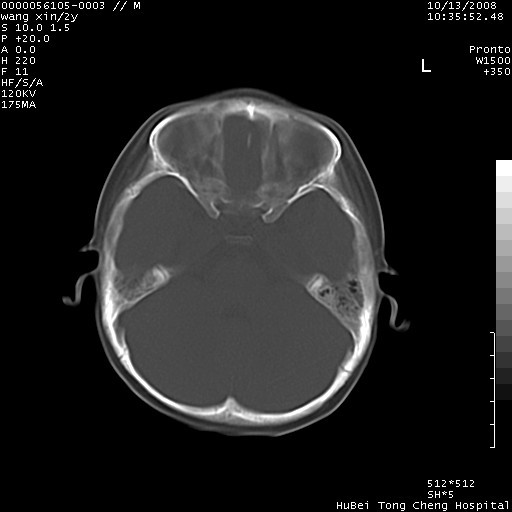

标题: PED1611:F,2Y。右侧额部小包块,光整,质硬,边界清楚,无 [打印本页]

标题: PED1611:F,2Y。右侧额部小包块,光整,质硬,边界清楚,无

病灶临近颅缝,支持考虑表皮样囊肿可能,病灶区要薄扫就好了

右额骨内板压迫性变薄,呈椭圆形膨胀性骨吸收和低密度区,其间可见小斑片状致密影,-支持表皮样囊肿